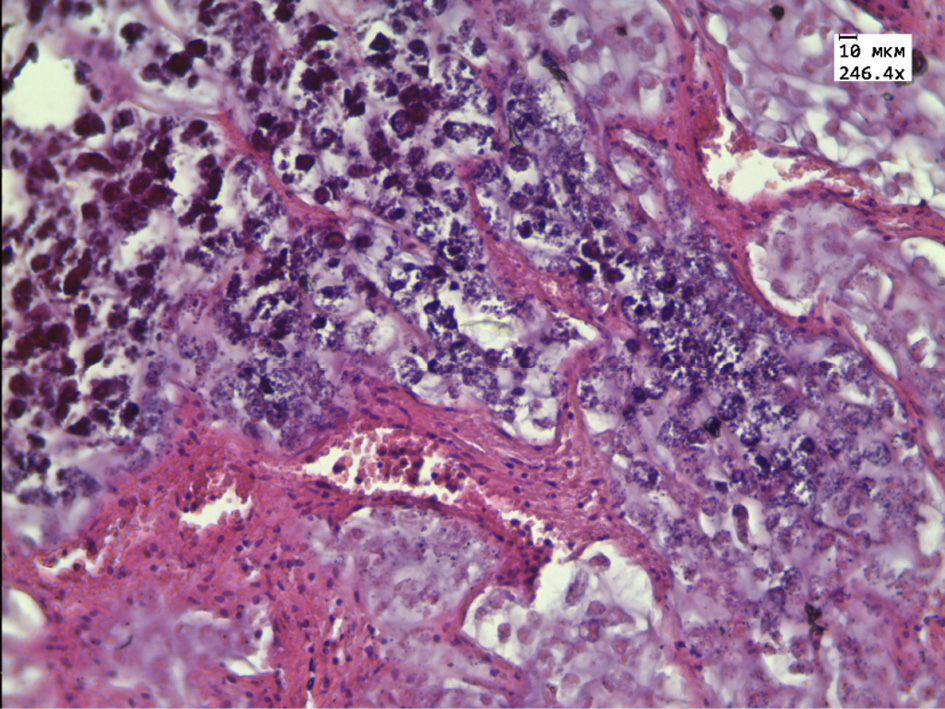

In the group of rats receiving aqueous extract of thyme, the tumor is represented by small rounded cells with a reduced flattened nucleus located on the periphery of the tumor tissue. The central parts are represented by extensive necrotic foci, a large number of “shadow cells” and thickened connective tissue partitions with a large number of blood vessels, as well as extensive clusters of tumor cells with signs of karyopycnosis, nuclear chromatin condensation and karyorexis, and a large number of apoptotic cells (Fig. 3, 4).

Figure 4 – Histological structure of transplanted hepatic cancer in the group receiving aqueous extract of Thymus marschallianus Willd.

Note: nuclear chromatin condensation and karyorexis in tumor cells (white arrow). Stained with hematoxylin and eosin. Magnification 246.4×